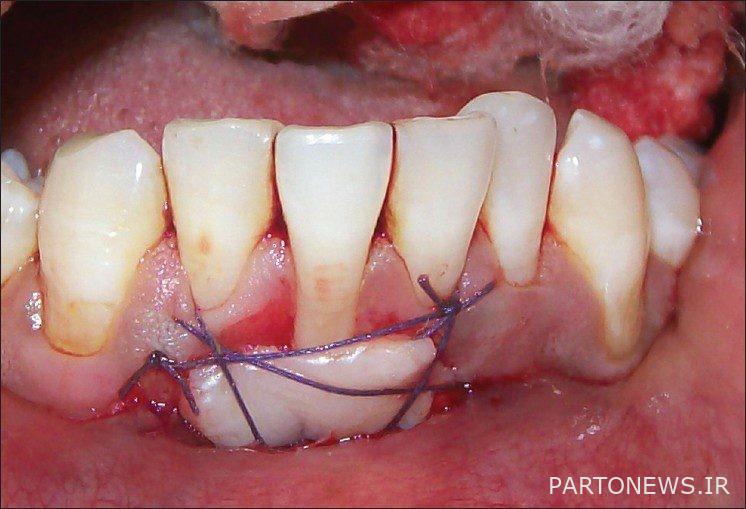

Gum diseases can be easily treated if they are diagnosed at the right time. Gum surgery is performed on an outpatient basis in the dentist’s office. This surgery is usually performed when infection or periodontitis is observed in the patient’s gums. The use of some drugs, the presence of cysts or tumors, the accumulation of plaque and bacteria around the gums, and severe infections are among the most important factors that lead to gum surgery.

In this method of gum surgery, the dentist makes an incision on the gum surface in order to remove the bacteria and contamination in that area. Then, by using bone grafting and stimulating proteins, it regenerates the gum tissue.